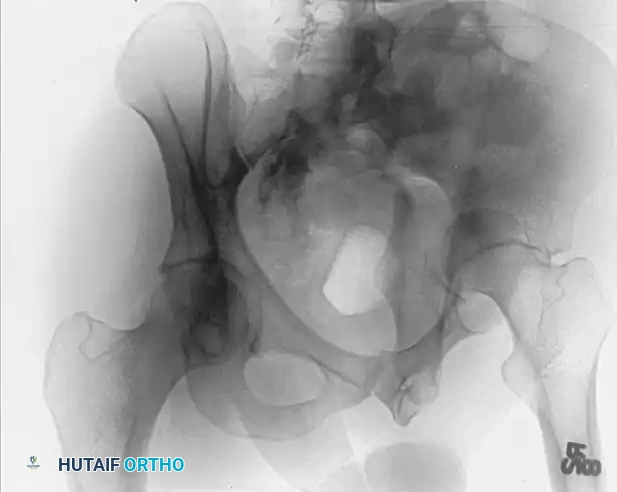

The Iliac Oblique View

In the iliac oblique view, the patient is rolled 45 degrees toward the uninjured side (elevating the injured hip). The radiographic beam is directed roughly perpendicular to the iliac wing of the affected side.

* Primary Structures Visualized: This view places the iliac wing en face, providing an excellent profile of the posterior column and the anterior wall of the acetabulum.

* Diagnostic Utility: It is critical for identifying fractures traversing the sciatic notch, assessing the integrity of the posterior column, and evaluating anterior wall comminution.

The Obturator Oblique View

In the obturator oblique view, the patient is rolled 45 degrees toward the injured side (elevating the uninjured hip). The radiographic beam is directed roughly perpendicular to the obturator foramen of the affected side.

* Primary Structures Visualized: This view places the obturator ring en face, providing a true profile of the anterior column and the posterior wall of the acetabulum.

* Diagnostic Utility: It is the definitive view for assessing the iliopectineal line's distal extent, the obturator ring, and the size and displacement of posterior wall fracture fragments.